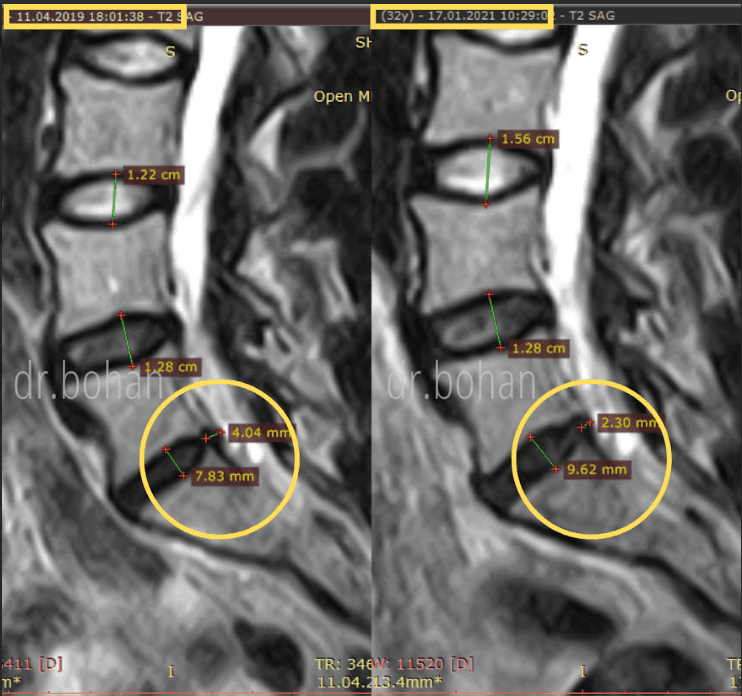

Метод лікування грижі шляхом стимуляції резорбції в Україні був впроваджений у 2020-2021 роках.  Алгоритм оцінки грижі на предмет резорбції, що використовується у клініках – є авторським, розроблений лікарем Боханом А.Ю.